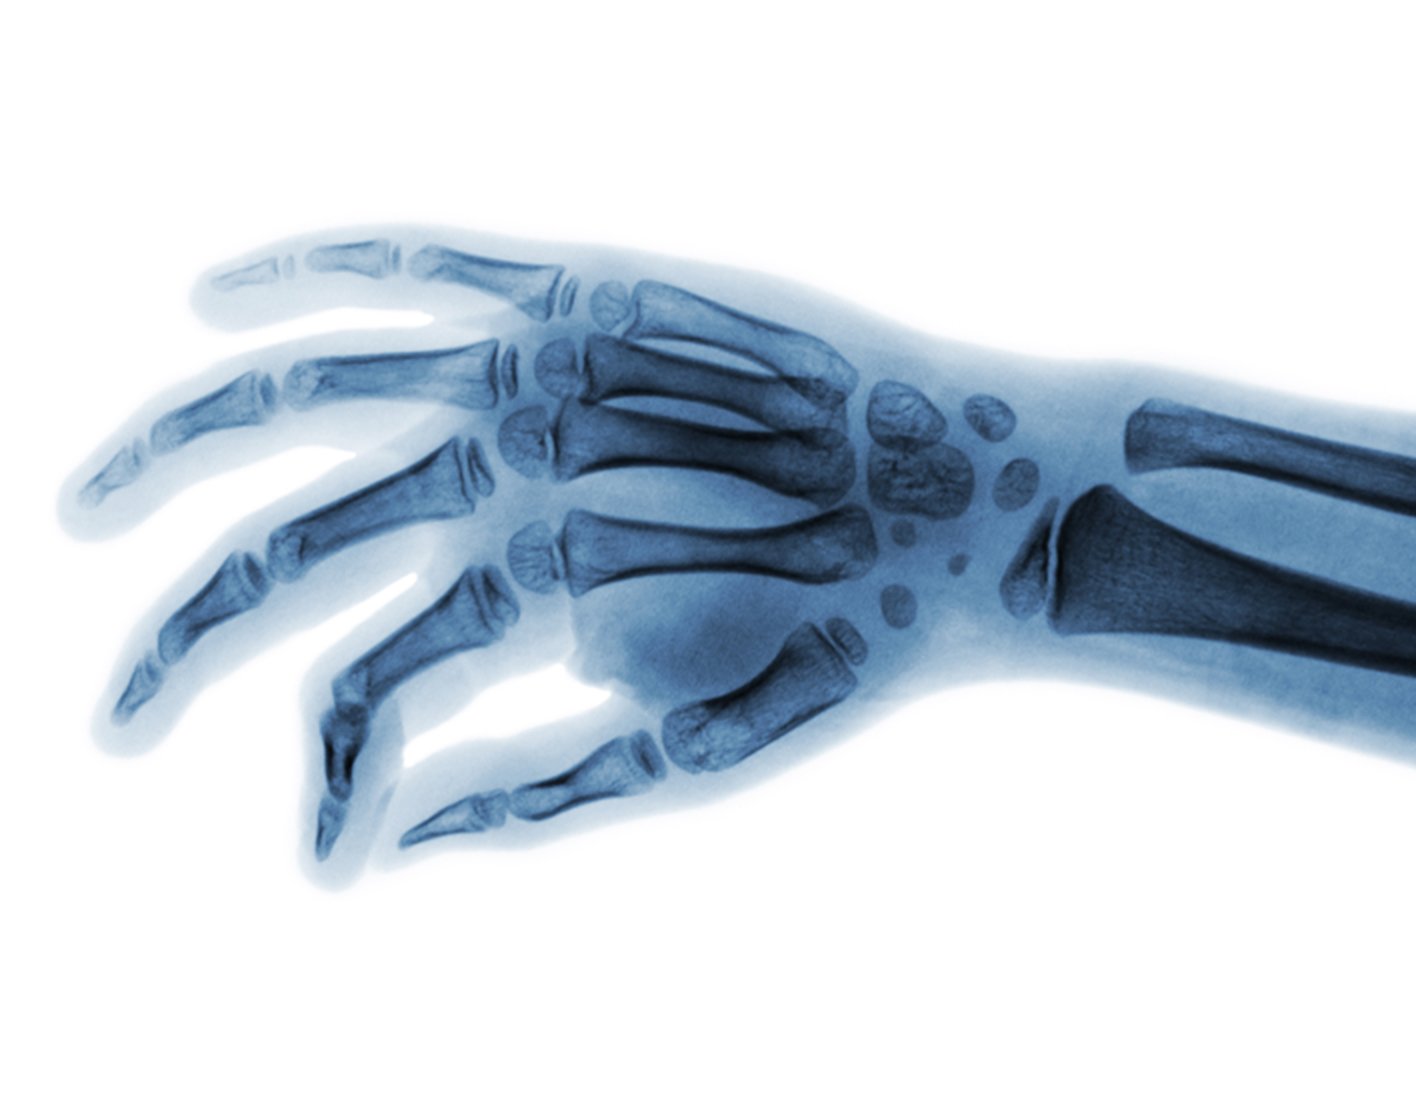

Hand x-ray

A hand x-ray is taken in a hospital radiology department or your health care provider's office by an x-ray technician. You will be asked to place your hand on the x-ray table, and keep it very still as the picture is being taken. You may need to change the position of your hand, so more images can be taken.